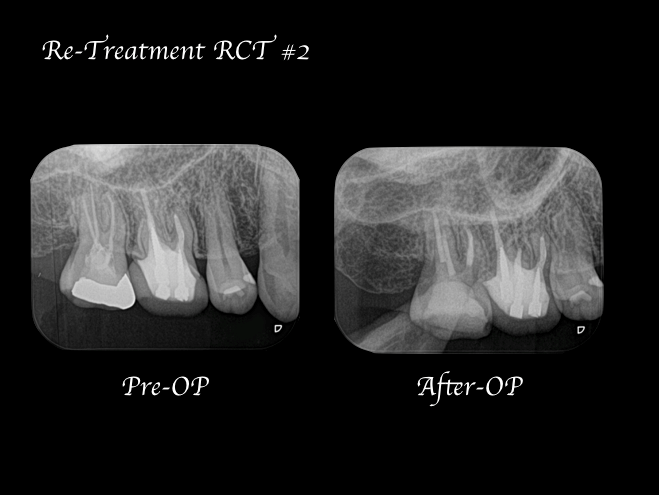

右上7番には臨床症状(叩くことでの痛み)が確認できるものの、レントゲン上には根尖性歯周炎と判断できる透過像(病変の影)は確認できませんでした。歯科用CTを撮影してみると、近心根と遠心根に明らかな病変を認めました(歯科用CT画像1赤丸)。他の臨床症状と歯科用CT画像から右上7番の根尖性歯周炎と診断しました。

治療中に歯科用顕微鏡(マイクロスコープ)下にてCT画像で確認した部位には手つかずの根管を確認し、処置を行った。

治療後の様子

治療回数は2回で終了しています。2回目の治療終了時には初診時で患者様が訴えていた違和感は改善され、次週、問題なければ仮歯の製作に移行する予定。